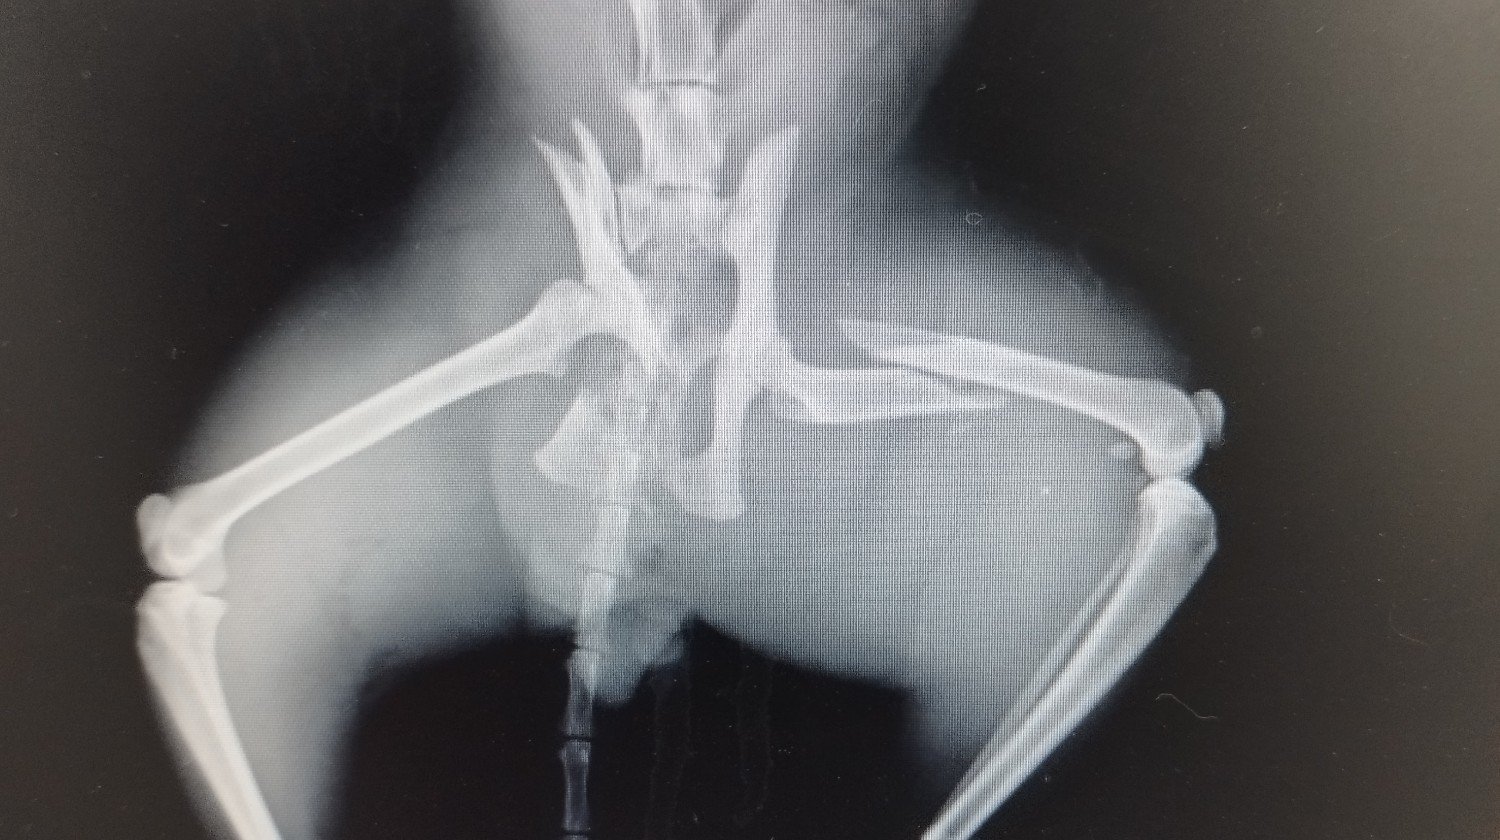

Romeu.

Romeu, Romeu, porque é que havias de ser Romeu? Porque é que partiste uma bacia e uma perna?

O Romeu devia fazer um raio-X para ver como está a pélvis e a perna.

As radiografias revelaram uma fratura da bacia e do fémur (a perna, ou seja, ao nível do ... "gomo").